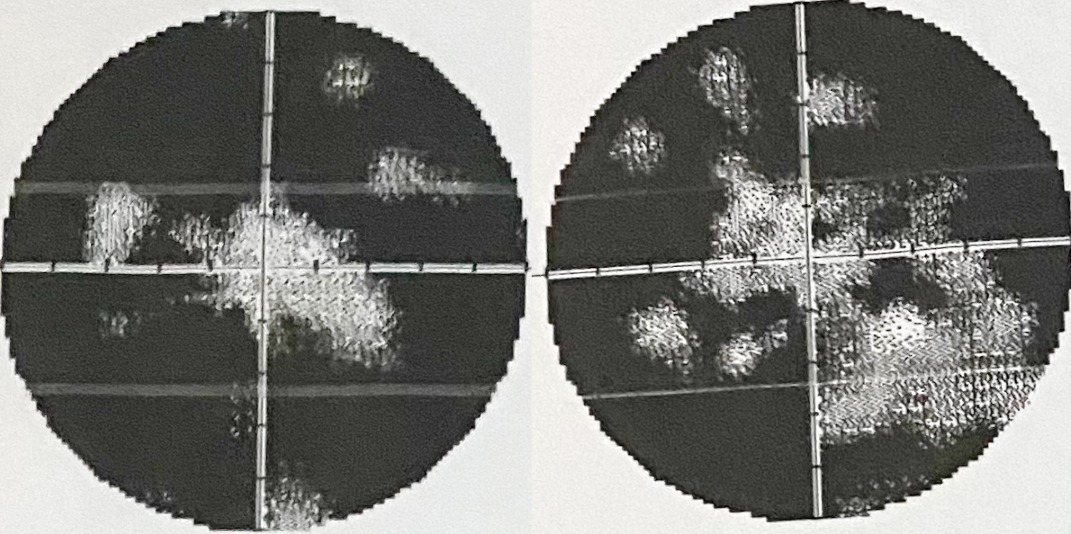

Візуаліізація зорового нерва

При офтальмолскопії можна виявити набряк зорвого нерва, крововиливи. Комп’ютерна периметрія важлива для функціональної діагностики.